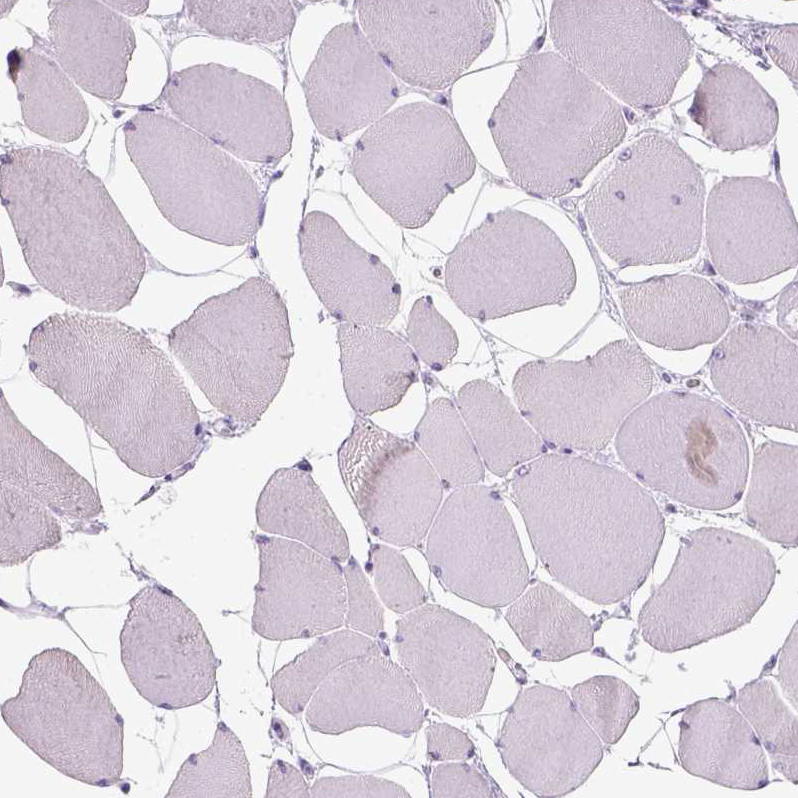

Immunohistochemistry analysis in human urinary bladder and fallopian tube tissues using HPA022261 antibody. Corresponding CYP24A1 RNA-seq data are presented for the same tissues.